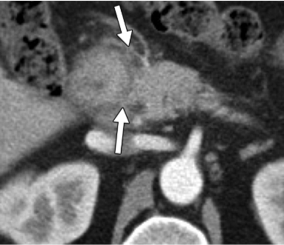

- A. Circumferential irregular submucosal wall thickening noted in D2 and D3 segment of duodenum causing luminal narrowing.

- B. Few hypoenhancing areas within the medial wall of duodenum. Uncinate process of pancreas appears oedematous.